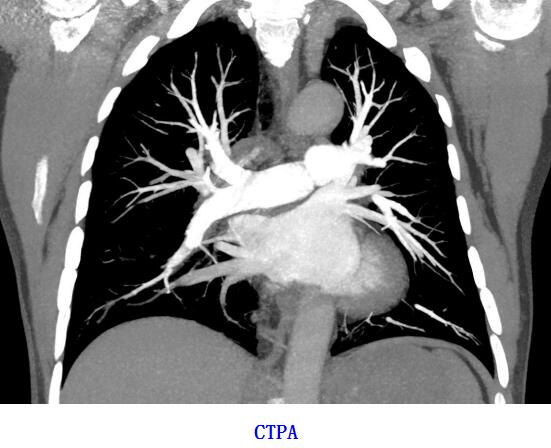

此CT机能够满足全身各系统的常规平扫及增强检查;全身血管CTA、CTV检查;三维检查,还配备肺功能测定、齿科检查、头颅及体部灌注等特殊软件,为临床提供了更为丰富的检查手段。

1、CT血管造影(CTA):可以评估血管及脏器功能,准确判断出血、栓塞、血管瘤、血管畸形、血管狭窄,肿瘤供血等情况,为治疗提供有效帮助。